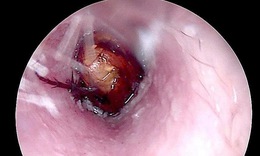

Cứu người bị áp xe ổ bụng hiếm gặp do mắc xương cá

Tin nóng y tế - 09/10/2025 20:05SKĐS - Chiều 9/10, Bệnh viện Lê Văn Việt (TPHCM) cho hay, các bác sĩ khoa Ngoại Tổng hợp vừa phẫu thuật thành công một ca áp xe ổ bụng do dị vật xương cá có thể nguy hiểm đến tính mạng nếu chậm trễ xử trí.